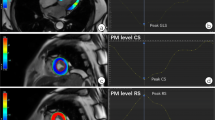

Summation of the volumes per slice of areas of hyperenhancement was outlined, allowing calculation of total infarct size (% LV myocardium). PMI was evaluated by LGE cardiac MRI images. Cine images of the same location were used as a side-by-side reference for localizing the PM within the blood pool during interpretation of contrast-enhanced images. PMI was considered present if any papillary hyperenhancement was present on LGE images. PMI was further categorized by location (anterolateral PMI and/or posteromedian PMI) and extent (partial (≤50 % hyperenhanced papillary myocardium) or complete (>50 % hyperenhanced papillary myocardium) on LGE short-axis images (Fig. 1) [11].

Assessment of PMI by LGE cardiac MRI. Patient with inferolateral STEMI with complete infarction of the posteromedian PM. A LGE image. B Cine image of the same location as a side-by-side reference for localizing the PM within the blood pool during interpretation of contrast-enhanced images. Patient with inferior STEMI and partial infarction of the posteromedian PM. C LGE image. D Cine image. Patient with anterolateral and inferior STEMI and combined partial infarction of the anterolateral PM and complete infarction of the posteromedian PM. E LGE image. F Cine image. (AL)PM (anterolateral) papillary muscle, LGE late gadolinium-enhancement, MRI magnetic resonance imaging, PMI papillary muscle infarction, (PM)PM posteromedian papillary muscle, STEMI ST elevation myocardial infarction

Left atrial volume was calculated using the summation of slices method multiplied by slice thickness. Left ventricular end-diastolic diameter (LVEDD) and left ventricular end-systolic diameter (LVESD) were measured in the short-axis view at mid-LV level. Additionally, the systolic sphericity index (SSI) (ratio of LV width to length) was measured in the four-chamber view at end-systole. Interpapillary muscle distance (IPMD) was measured in the short-axis view at end-systole. On the stack of short-axis cines, the endocardial and epicardial borders were outlined in end-systolic and end-diastolic images. Left ventricular end-diastolic volume (LVEDV) and left ventricular end-systolic volume (LVESV) were calculated using the summation of slice method multiplied by slice thickness. LVEF was calculated as LVEF = 100 % × (LVEDV-LVESV)/LVEDV. Regional LV contractile function was graded with the wall motion score index (WMSI) using a 17-segment, 5-point scoring system (1 = normal contraction; 2 = hypokinesia; 3 = akinesia; 4 = dyskinesia; 5 = aneurysmatic).

Mitral annular diameter, tethering height (distance between the leaflet coaptation point and the mitral annular plane), tethering area (area enclosed between the annular plane and the mitral leaflets) posterior tethering angle, and anterior tethering angle were measured in the 3-chamber view (mid-systolic) (Fig. 2) [9].

Evaluation of interpapillary muscle distance, mitral valve geometry, and CIMR severity. A evaluation of interpapillary muscle distance measured with cardiac MRI in the short-axis view (end-systolic). B, C Evaluation of mitral valve geometry with cardiac MRI in the 3-chamber view (mid-systolic); mitral annular diameter (a–c), tethering height (d–b), tethering area (area enclosed by a–b–c), posterior tethering angle (angle between c–a and c–b), anterior tethering angle (angle between a–c and a–b). D Evaluation of CIMR severity with TTE in the apical four-chamber view (mid-systolic) (jet area/LA area). AD annular diameter, ALPM anterolateral papillary muscle, Ao aorta, ATA anterior tethering angle, CIMR chronic ischemic mitral regurgitation, IPMD interpapillary muscle distance, LA left atrium, LV left ventricle, MV mitral valve, PMPM posteromedian papillary muscle, PTA posterior tethering angle, TA tethering area, TH tethering height